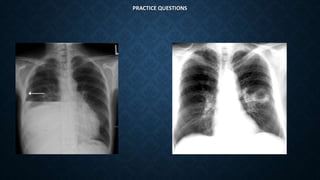

PRACTICE QUESTIONS